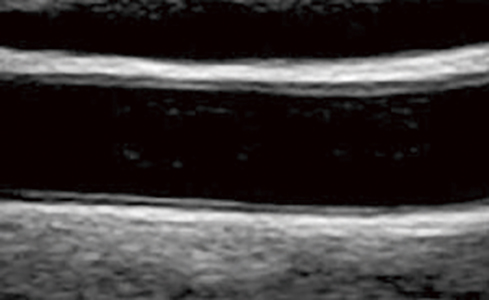

正常な状態の血管

狭くなった血管(上部黄色がプラーク)

頸動脈エコー検査は、超音波を使用し、頸動脈の動脈硬化の程度を調べる検査です。頸動脈は動脈硬化が起こりやすい場所で、進行すると血管が細くなり、やがて閉塞し脳卒中を引き起こします。MRAではわからないこの動脈硬化を初期の段階でとらえることが可能です。。